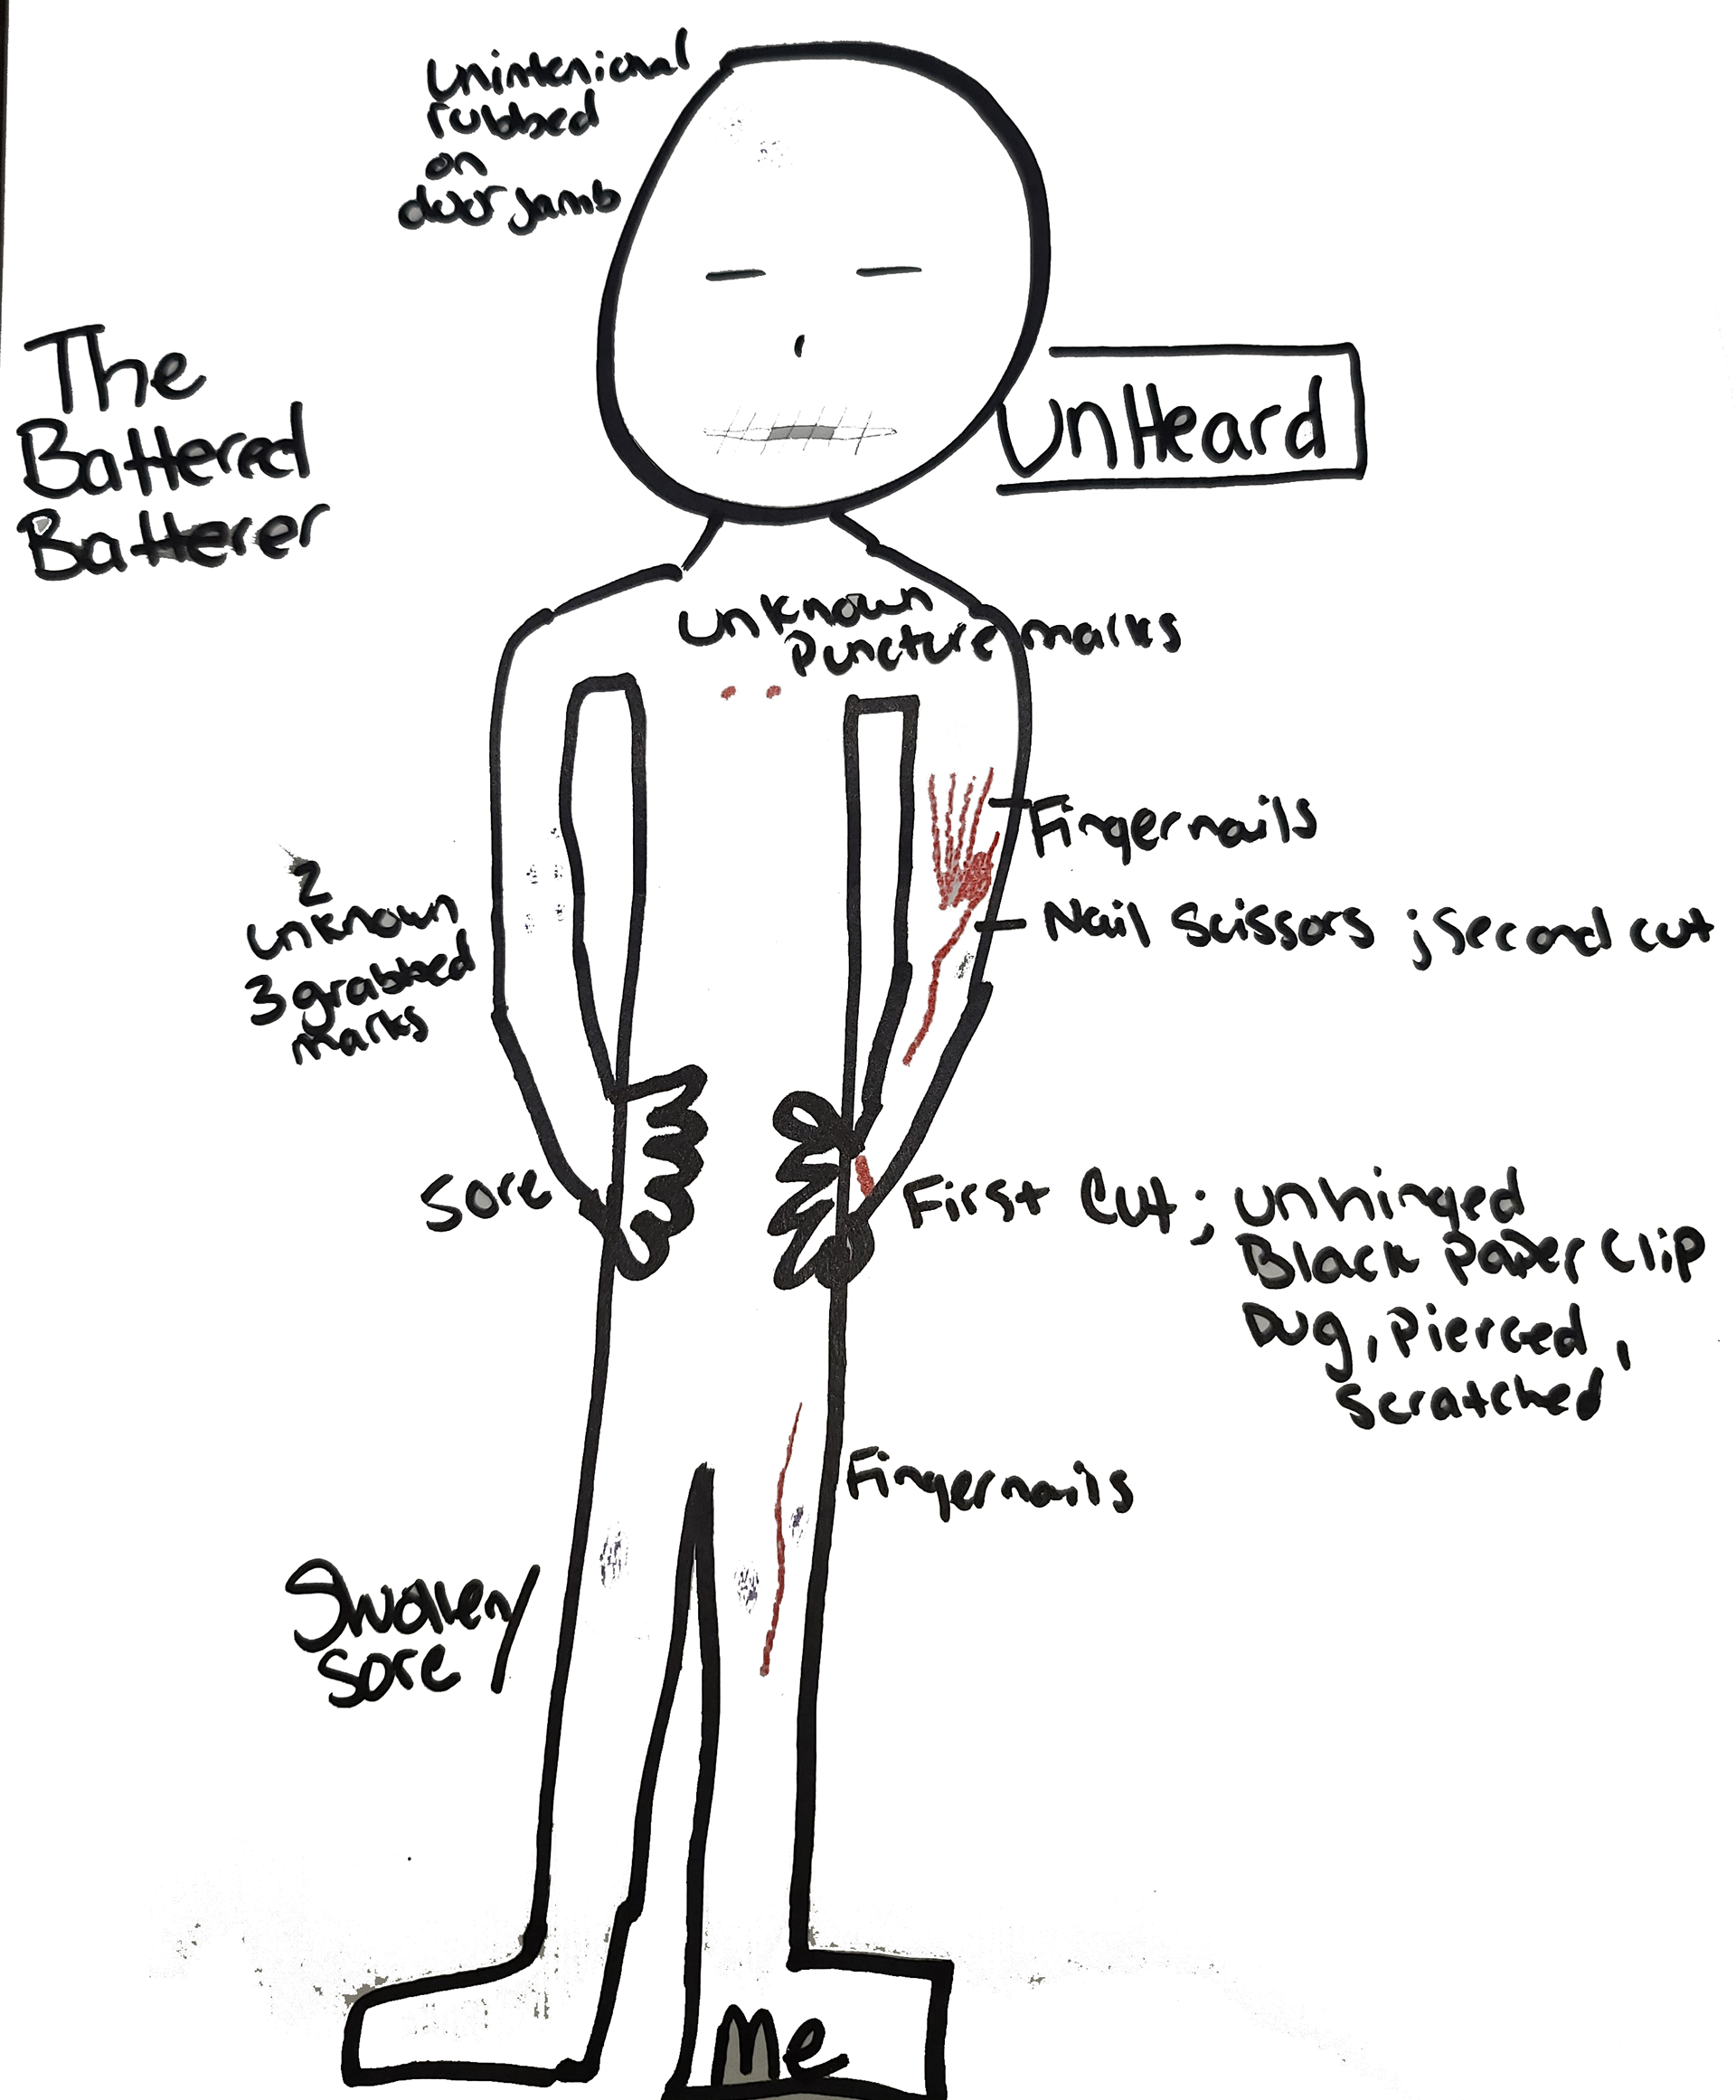

HOPE WEISS

HOPE WEISS

HOPE WEISS

HOPE WEISS

HOPE WEISS

HOPE WEISS